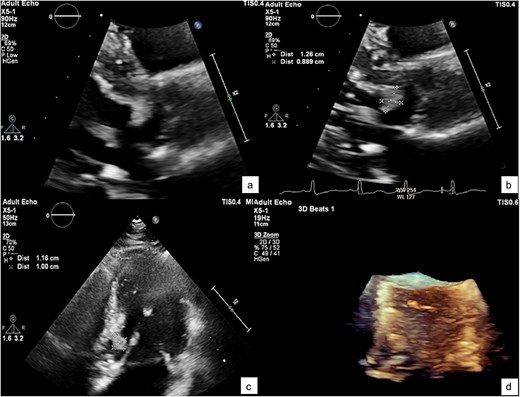

A TTE showing a small-rounded mass attached to the LV septum (arrow), which can be seen protruding into the LVOT in various echocardiographic views: Parasternal view (a), parasternal long axis view (b), 5-chamber view (c), and short-axis view of aortic valve (d).

He was referred to our hospital for further evaluation by the cardiology and cardiothoracic surgery departments. On admission, he was afebrile with a heart rate of 62 beats per minute, blood pressure of 148/73 mmHg, and respiratory rate of 20 breaths per minute. No abnormalities were noted in any other system. Laboratory findings were unremarkable. An ECG demonstrated normal sinus rhythm. TTE re-evaluation revealed a normal LVEF of 72% with a 1.2 × 1 cm hypermobile cardiac mass attached to the basal anteroseptal wall near the LVOT without evidence of LVOT obstruction; there were no valvular lesions or thrombus seen (Figs 1 and 2). Coronary angiography showed normal coronary vessels. Due to its nature and clinical presentation, the patient was set for early surgical excision of the mass 3 days after admission.